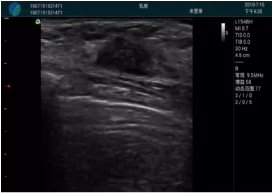

清晰顯示腺體內(nèi)低回聲快影,邊界清晰,包膜較光滑

確定進針路徑并實時監(jiān)測抽吸針與腫塊位置關(guān)系

抽吸針進入腫塊內(nèi)部進行旋切

抽吸過程中可見腫塊明顯縮小,并根據(jù)腫塊位置改變針道位置

抽吸旋切后再進行超聲復查,原腫塊區(qū)域未見殘留組織及出血